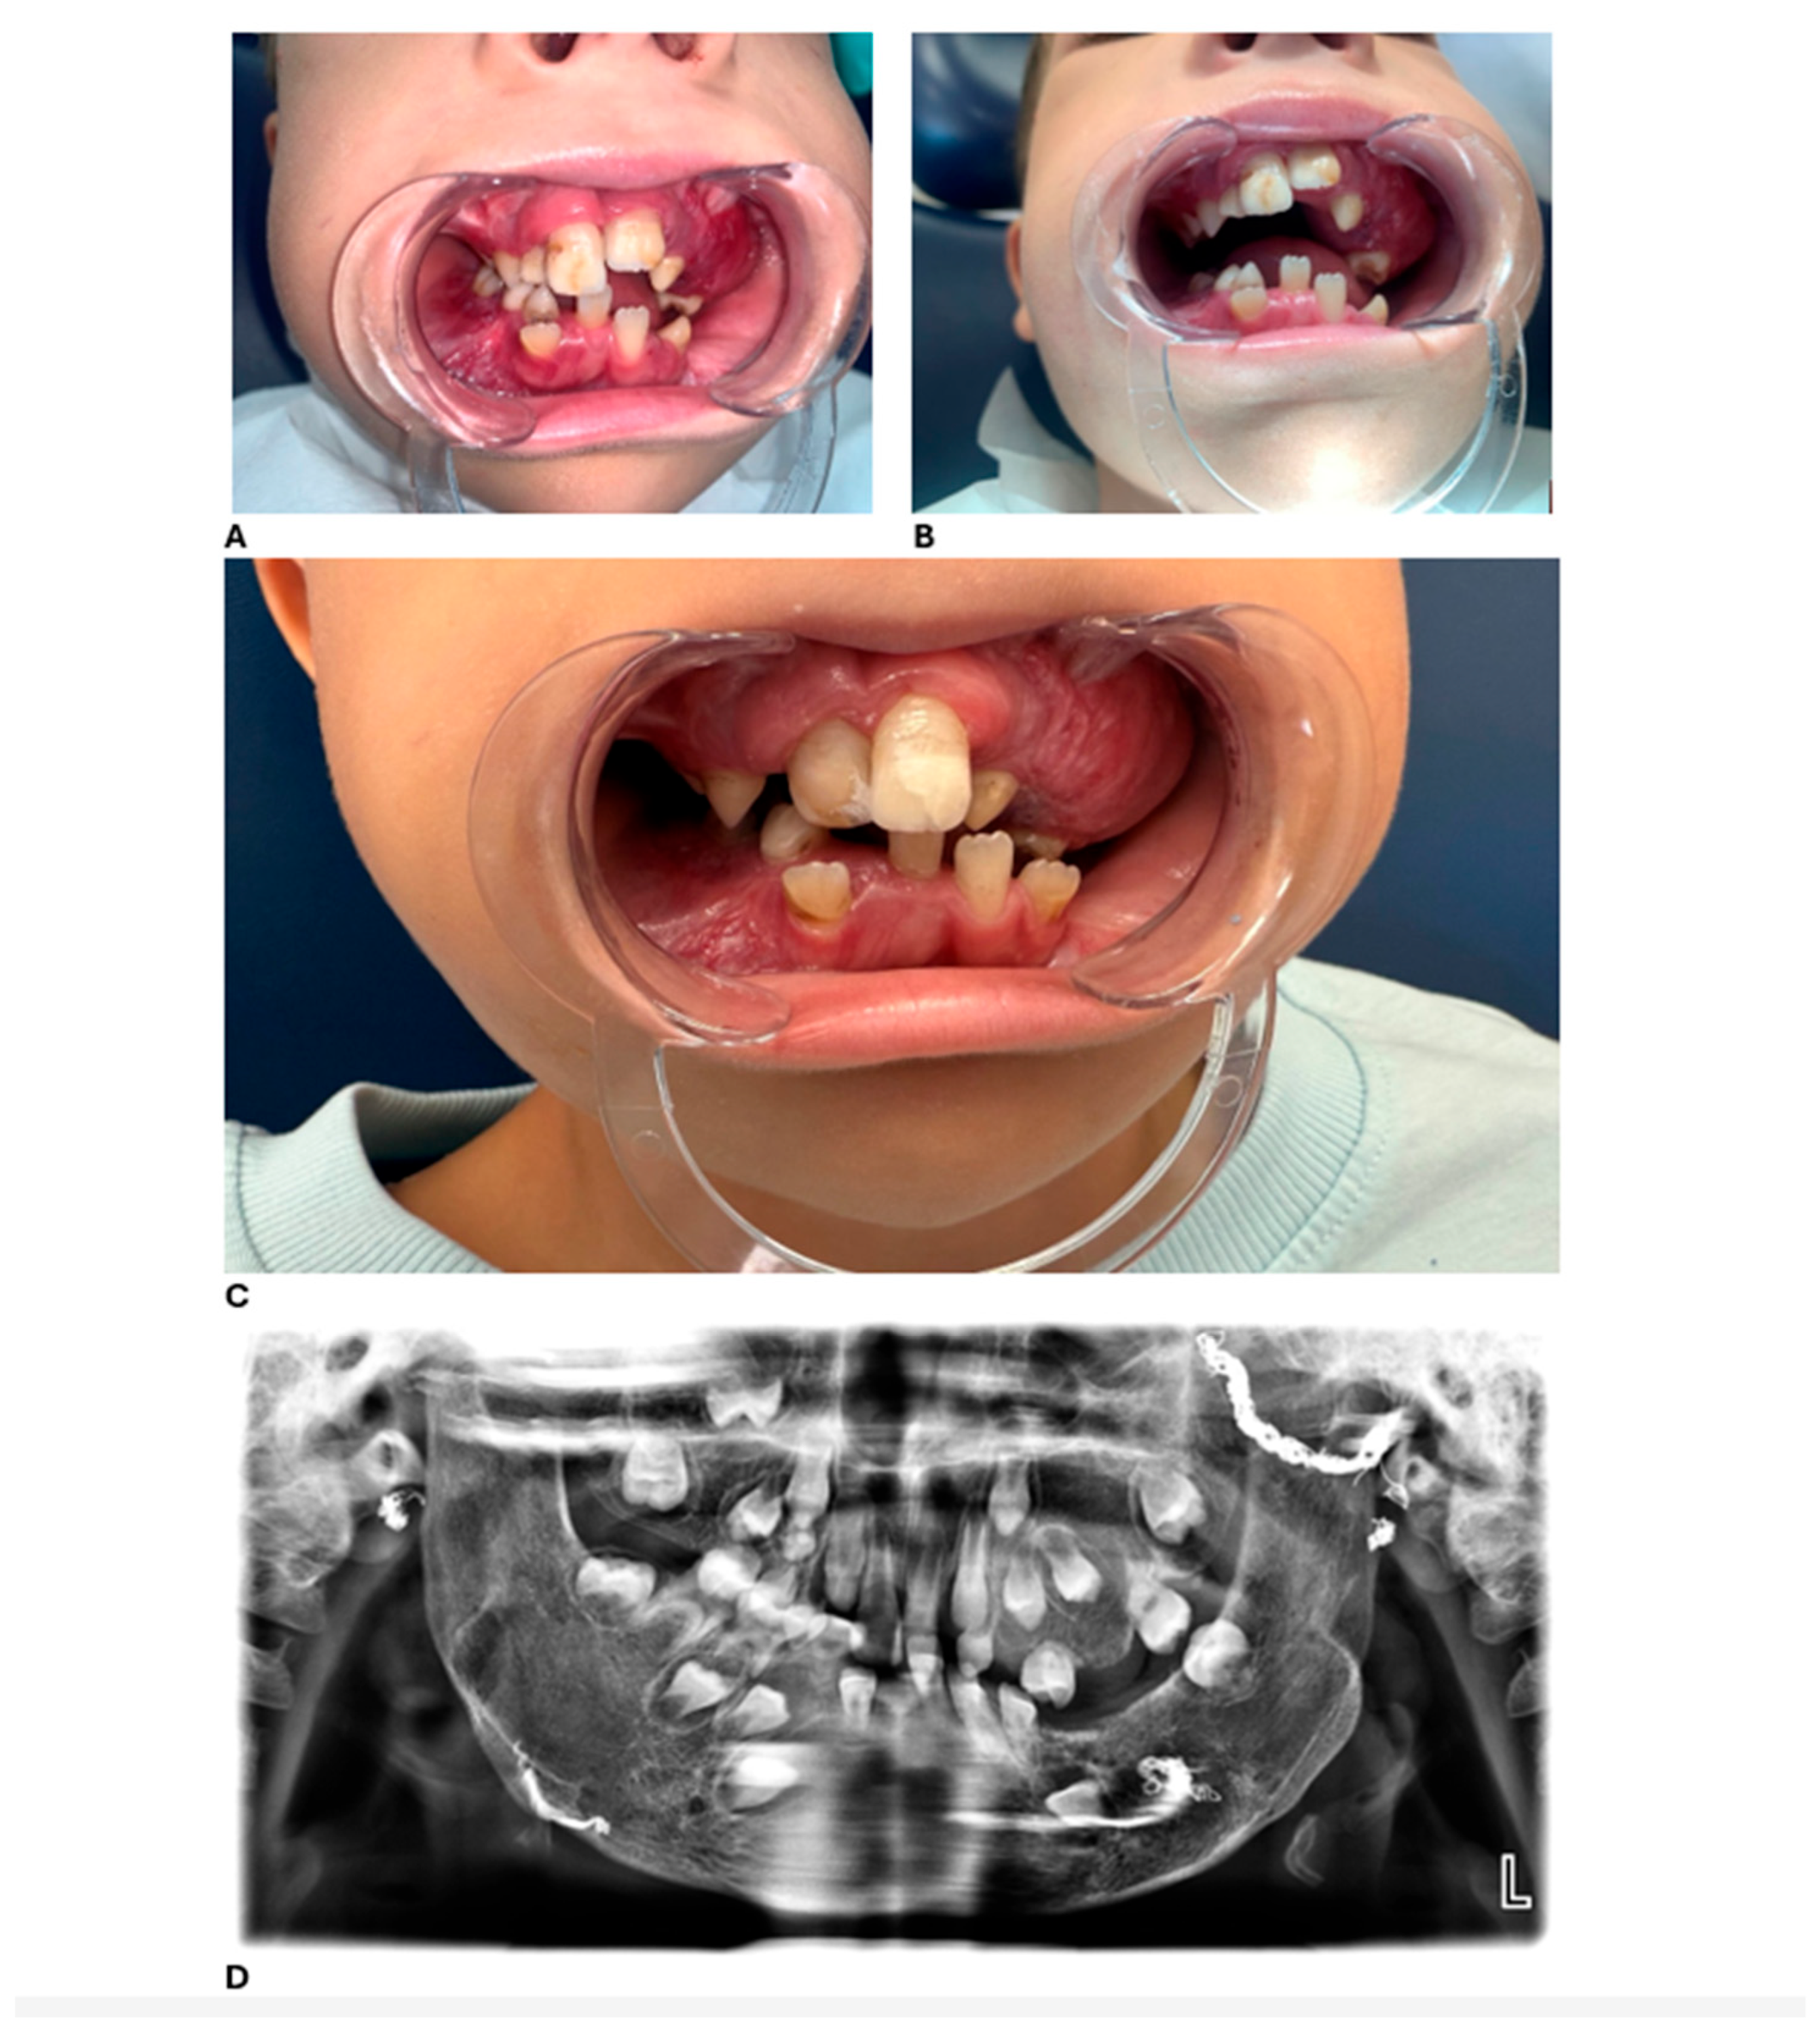

During the initial dental examination at age four, intraoral swelling was noted in multiple areas. These lesions did not impair feeding but caused concern for caregivers. No pain, fever, or systemic signs were reported. Clinical findings included the following:

• Multiple hemangiomatous lesions located in both maxillary and mandibular regions, predominantly in the upper left posterior quadrant.

• Firm gingival hypertrophy in the upper left quadrant.

• Traumatic avulsion of primary tooth 51 (due to scooter fall).

• Mixed dentition with partial edentulism due to prior surgical extractions; no cases of agenesis were identified.

• Presence of significant subgingival plaque.

• Cervical caries on tooth 83 with enamel loss and exposed dentin.

• Mildly coated tongue.

These clinical features are illustrated in Figure 1, showing intraoral and extraoral views as well as radiographic findings.

The panoramic image also indicates potential future dental challenges, such as delayed or ectopic eruption of permanent teeth, malocclusion, and enamel defects. Recognizing these risks early allowed us to plan preventive monitoring and timely interventions. Overall, these clinical and radiographic findings underscore the critical role of routine dental assessments in detecting early manifestations of systemic vascular anomalies, enabling timely diagnosis and multidisciplinary intervention.

Figure 1. Intraoral and extraoral clinical images at the initial examination (age 4). (A) Intraoral view showing gingival overgrowth in the upper molar region. (B) Extraoral frontal view demonstrating facial asymmetry and prominent cheeks. (C) Panoramic radiograph showing multilocular radiolucent lesions within alveolar bone.